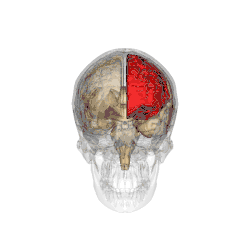

Functional magnetic resonance imaging (fMRI) scans of the brains of subjects exposed to thirty-five hours of sleep deprivation indicate that sleep deprivation is related to increases in prefrontal cortex and parietal lobe activation during tasks that combine verbal learning and arithmetic. This is particularly apparent in the right hemisphere. In non-sleep-deprived people involved in verbal learning and arithmetic tasks, the anterior cingulate cortex and the right prefrontal cortex are active. Following sleep deprivation, there is increased activation of the left inferior frontal gyrus and the bilateral parietal lobes. This information suggests that divided attention tasks require more attentional resources than normally required by a non-sleep-deprived person.[5]

Deficits in cognitive performance due to continuous sleep restriction are not well understood. Studies have looked into physiological arousal of the sleep-deprived brain. Participants, whose total amount of sleep had been restricted by 33% throughout one week, were subjected to reaction time tests. The results of these tests were analyzed using quantitative EEG analysis. The results indicate that the frontal regions of the brain are first to be affected, whereas the parietal regions remain active until the effects of sleep deprivation become more severe, which occurred near the end of the week. EEG and ERP analysis reveals that activation deficits are more apparent in the non-dominant hemisphere—than in the dominant hemisphere.[11]

Lack of sleep changes how genes are expressed and interferes with neurobiological functions that are necessary for cognitive function. Research indicates a decline in the expression of proteins that are essential for memory consolidation and synaptic plasticity, including CREB and PKCγ. These molecular abnormalities damage the cerebellum and hippocampus, which results in deficiencies in long-term memory functions and spatial working memory. Chronic sleep deprivation also raises the brain's amyloid-beta aggregation, which is linked to neurodegenerative diseases like Alzheimer's. Impaired clearance mechanisms during reduced sleep worsen this neurotoxic environment. Neuroimaging studies also show a shift of cognitive resources, which decreases activation in the prefrontal cortex and parietal lobes and increases activation in areas like the thalamus. However, this compensating strategy is not enough to sustain the best possible cognitive function throughout extended periods of wakefulness.[61][62]